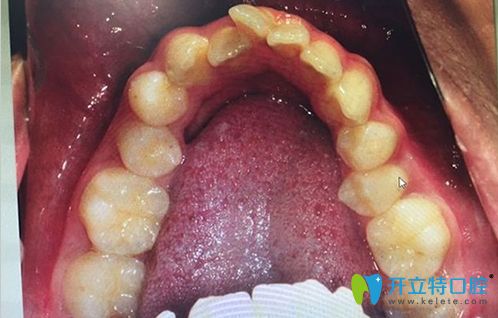

牙弓狹小需要擴(kuò)弓的病例圖